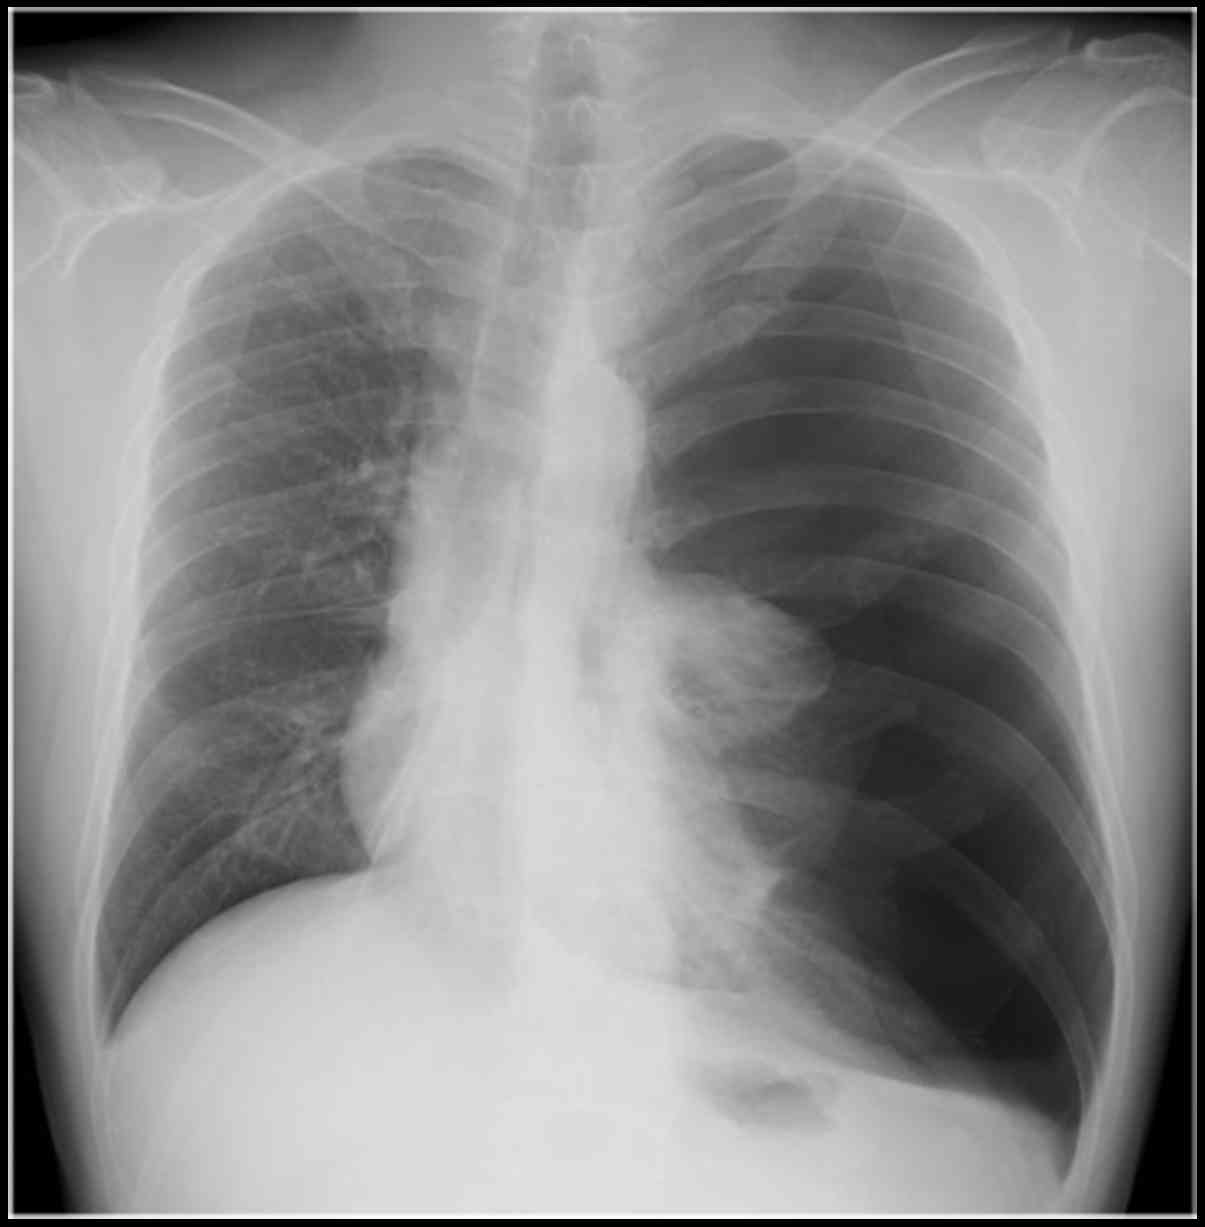

Plain radiography and CT displayed spontaneous pneumothorax in the left lung (Fig. 4). Chest tube placement and pleurodesis in the right lung were performed. Complete pulmonary expansion was achieved. Thereafter, he began receiving chemotherapy again, and 2 years have passed since the recovery from pneumothorax. At the last follow-up, the patient was living with multiple cystic pulmonary metastases, and he developed bone metastases in the rib, sacrum, and left femur; cystic pulmonary metastases gradually appeared, and radiotherapy was administered to each bone metastasis.

Figure 4.

Plain radiograpy showing pneumothorax in the left lung.